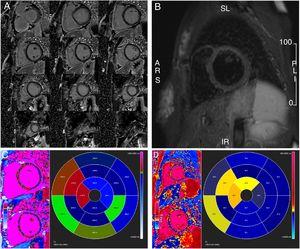

One month later, repeat TTE revealed LV recovery (LVEF 63%, GLS -21% with apparent improvement in basal segments, trivial MR) (Figure 1B, Table 1 and Video 1). Meanwhile, cardiovascular magnetic resonance showed no late gadolinium enhancement and normal T2-weighted short tau inversion recovery imaging, while T1 and T2 mapping were consistent with low-grade edema at the basal septum where systolic dysfunction was noted in the acute setting (Figure 3). Indexed LV end-diastolic and end-systolic volumes were 110 ml/m2 and 33 ml/m2, respectively (LVEF 70%).

Cardiovascular magnetic resonance one month after the acute phase. (A) Gadolinium study with no late enhancement; (B) T2-weighted short tau inversion recovery imaging showing no residual macroscopic myocardial inflammation or edema; (C) T1 mapping study and (D) T2 mapping study showing low-grade septal edema.